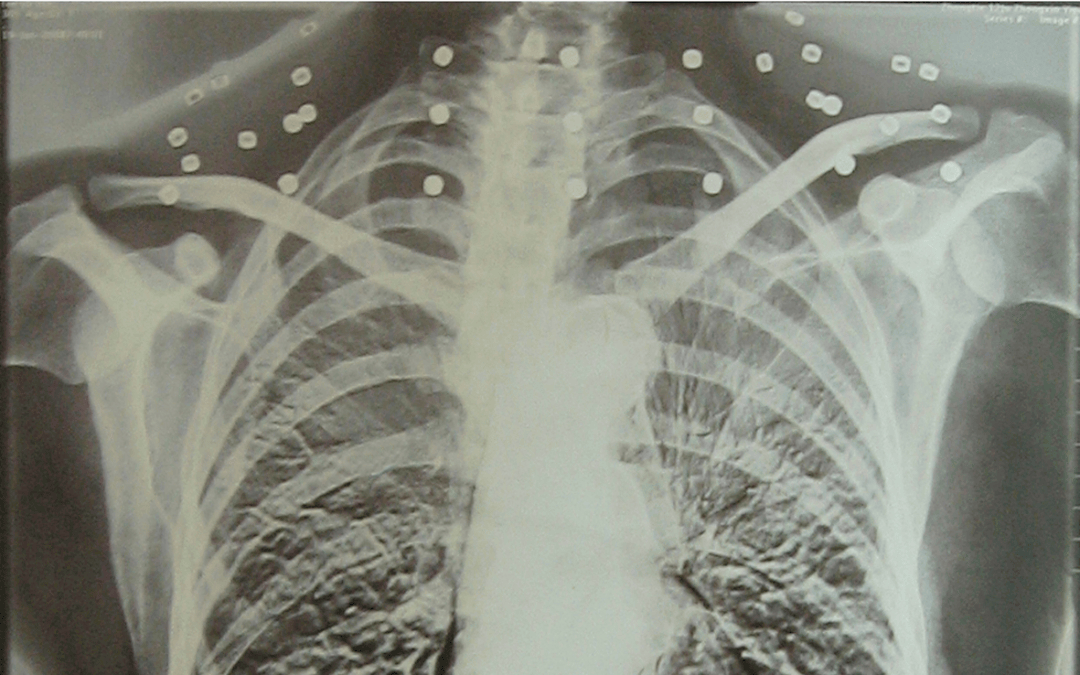

这张照片

是今年82岁的吴以先老人

拍摄的一张CT照

但实际上是

吴以先的颈部和腹部

共分布着33枚弹片

但是打进身体里的弹片

一直留在了体内

他体内的弹片都没有取出

每到天气变化时

身体留有弹片的位置就有痛感

但吴以先不考虑取出弹片

在他看来

这是他与战友并肩作战的见证

是他的勋章